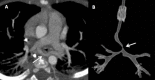

Congenital pulmonary artery anomalies represent a diverse group of abnormalities, ranging from asymptomatic incidental findings to causes of sudden cardiac death. While some may be recognized in childhood, others may be found incidentally in adulthood. We review the clinical and imaging findings in patients with congenital anomalies of the pulmonary arteries, including valvular and perivavular anomalies as well as abnormal narrowing, course and communications of the pulmonary arteries. We also discuss the role of various imaging modalities in the evaluation of these patients. It is vital to be aware of the key radiologic manifestations and associated haemodynamic consequences in these conditions in order to facilitate accurate diagnosis and prognostic stratification.